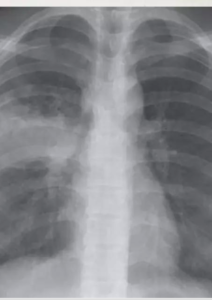

Sequelae of healed primary TB, but may be seen in 3-6 percent of cases of post primary tuberculosis as the main or only abnormality

calcified nodule consistent with a calcified granuloma. In addition, there is bilateral apical pleural thickening